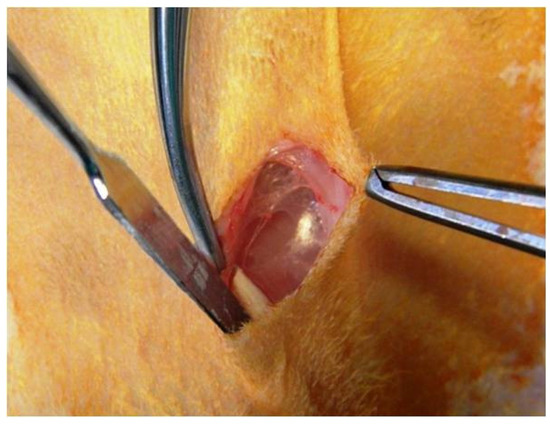

Immediately after animals were sacrificed [1], fragments of subcutaneous connective tissue were collected from biomaterial implant sites (Figure 3).

Figure 3. Samples selected for sampling: (AC) lax subcutaneous tissue after implantation of three biomaterials.